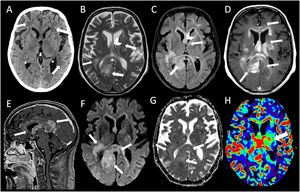

En una TC craneal (fig. 1A), se apreciaron hipodensidades parcheadas en sustancia blanca periventricular y subcortical en relación con cambios hipóxico-isquémicos crónicos, leucoaraiosis y discreto aumento del tamaño del sistema ventricular.

Múltiples lesiones hiperintensas en T2 (B) que de forma parcialmente confluente y expansiva afectan bilateralmente la sustancia blanca subcortical bifrontal, los centros semiovales y la corona radiata, la región gangliobasal y la sustancia blanca periventricular. También compromiso de la sustancia blanca profunda posterior del lóbulo temporal derecho. Las lesiones comprometen extensamente el cuerpo calloso en toda su extensión, el fórnix derecho, la comisura blanca anterior, cintillas ópticas bilaterales, el hipocampo derecho y el pedúnculo y tegmento mesencefálico izquierdo. Las lesiones tienen discreta hiperseñal a la difusión (F), y presentan un realce homogéneo y mal definido después de la administración del contraste (D,E). En el estudio de perfusión, alguna de las lesiones muestra aumento del volumen sanguíneo cerebral (H).

Durante su ingreso en UCI se practicó un fondo de ojo que no detectó la presencia de papiledema. La resonancia magnética (RM) mostró una afectación multifocal confluente bihemisférica de predominio central con extensión mesencefálica izquierda, cuyas características radiológicas sugerían como principal sospecha diagnóstica que se pudiera tratar de un linfoma cerebral (fig. 1B-H). La tomografia computarizada con emisión de positrones (PET/TC) mostró múltiples focos hipermetabólicos encefálicos concordantes con las lesiones descritas en la resonancia magnética y compatibles con un proceso linfoproliferativo de alto grado, SUV (Standarized Uptake Value) máxima de 10,9 (fig. 3). Debido a la situación clínica del paciente no fue posible realizar una biopsia cerebral para la obtención de material histológico.

Con relación al caso descrito, los procesos sistémicos fueron razonablemente descartados mediante las primeras pruebas realizadas durante su estancia en Urgencias (gasometría arterial, analítica general, radiografía de tórax y un sedimento urinario). Respecto a la neuroimagen, la TC craneal (fig. 1A) no evidenció alteraciones significativas en el parénquima cerebral con excepción de áreas hipodensas parcialmente confluentes en ambos hemisferios cerebrales (flechas) que sugerían cambios hipóxico-isquémicos crónicos. En las imágenes de RM cerebral (fig. 1B-H) se apreció la presencia de múltiples lesiones hiperintensas (flechas) en T2 (fig. 1B) y FLAIR (fig. 1C) con características confluentes en ambos hemisferios cerebrales con predilección en la región central donde se observa afectación del fórnix (cabeza de flecha) y cuerpo calloso (asterisco, *). En T1 después de la administración intravenosa de contraste (fig. 1D y E), la mayoría de las lesiones muestran un marcado realce (flecha). El estudio de difusión (fig. 1F) y mapa de coeficiente de difusión aparente (ADC-G) reveló que las zonas afectadas mostraban restricción heterogénea (flechas). El mapa de perfusión demostró un incremento del volumen sanguíneo cerebral (VSC-H) en la región talámica izquierda (flecha).